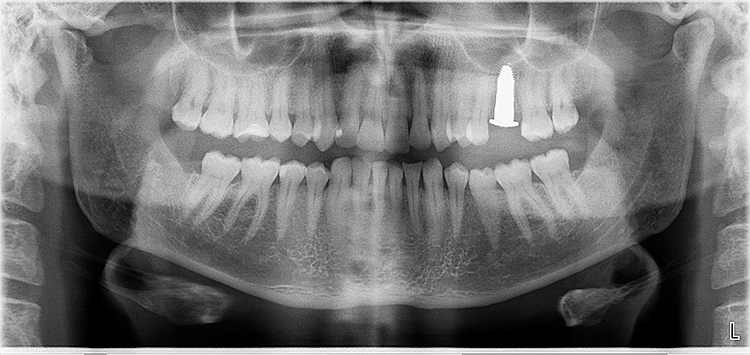

Abb. 4: Repräsentativer Fall von Grad A Typ III. a) Ansichten vor der Implantation. Röntgenbild der periapikalen Läsion an einem wurzelkanalbehandelten Molaren. b) Die Extraktionsalveole zeigt ein interradikuläres Septum vom Typ III (B).